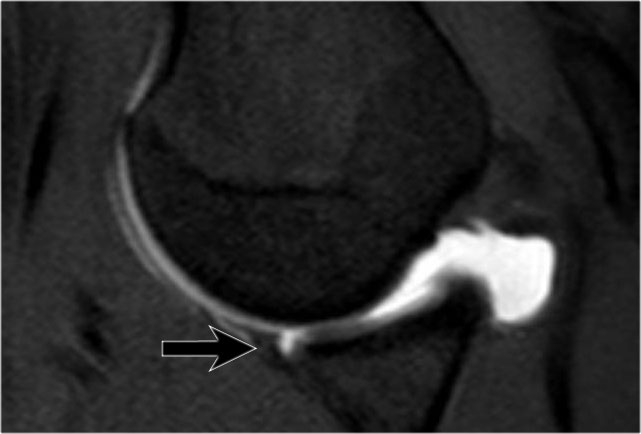

Đây là một bệnh nhân khác có Bankart xương được thấy trên bốn hình ảnh liên tiếp của MRI khớp cản từ ở tư thế ABER.

Lưu ý đường viền bất thường của ổ chảo phía trước và bờ trước bị avulsion (mũi tên)